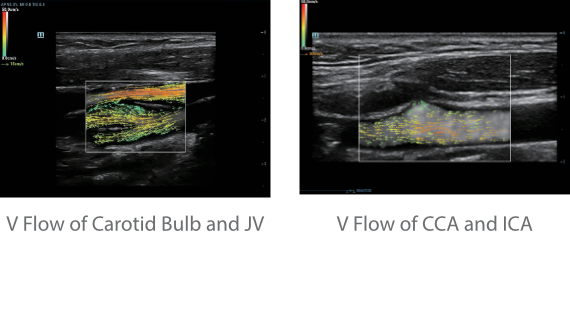

?? Resona 7? ???? ??? ?? ???? ??? ??? ???? ??? ?? ???? V Flow? ?? CNS ??? ?? 3D ??? ???? ?? ???? ?? ??? ?? ?? ?? ??? ??????. ???? ??? ??? ?? ?? ??? ??? ?? ?? ??? ??? Resona 7? ??? ???? ???? ??? ??? ??? ????.